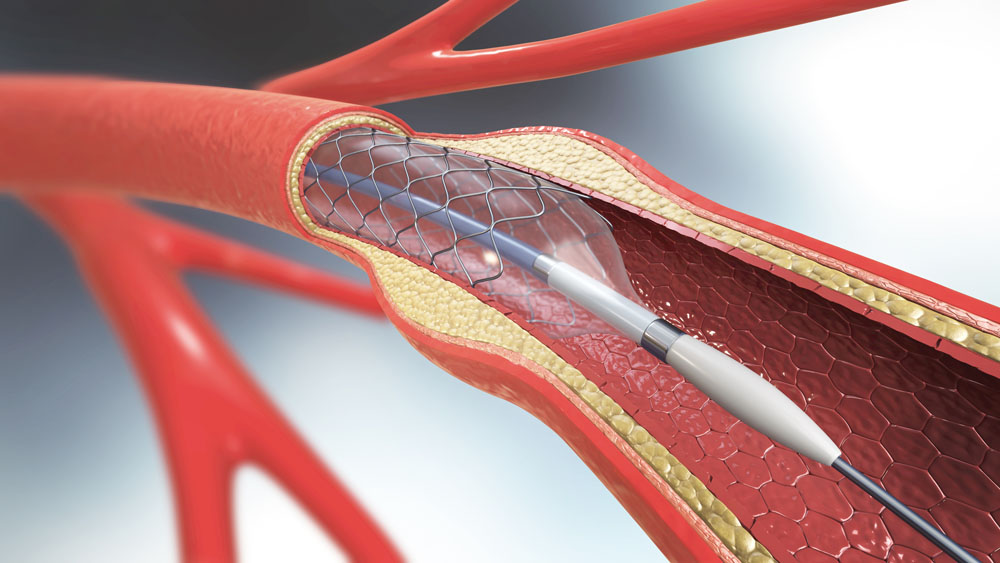

- Arteriovenöser Graft (AVG): Eine synthetische Röhre, die als Brücke zwischen Arterie und Vene dient, wenn die direkte Schaffung einer Fistel nicht möglich ist.